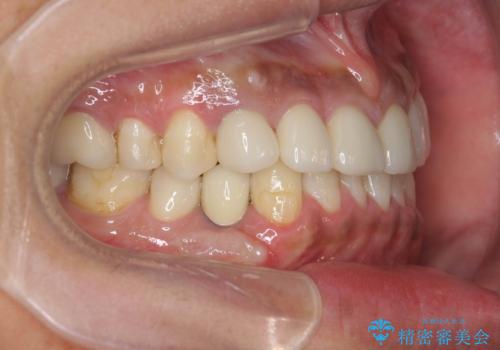

歯並びを整えたことで、歯ブラシのしやすさが向上し見た目も銀歯を全て除去したことで大きく改善して大変満足いただくことができました。